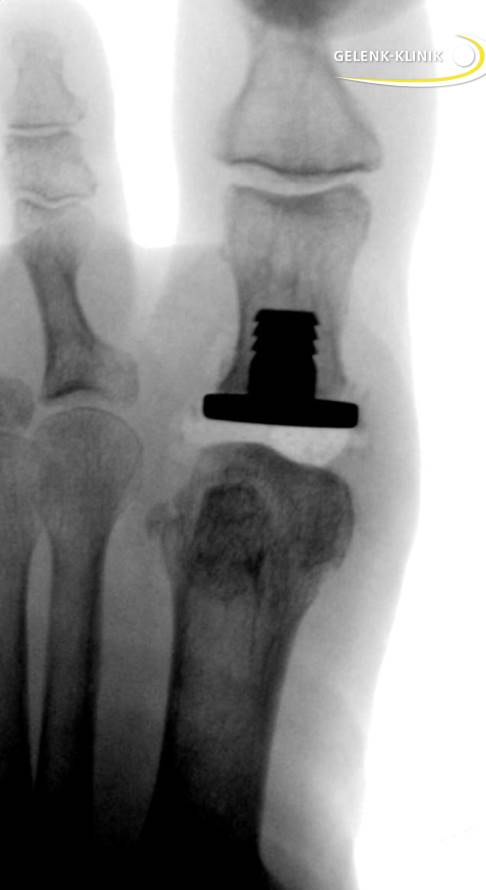

Röntgenbild einer Hemiprothese zur Behandlung einer Arthrose des Großzehengrundgelenks (Hallux rigidus). © Gelenk-Klinik

Eine Hemiprothese des Großzehengrundgelenks kann bei fortgeschrittenen Schäden am Gelenkknorpel eingesetzt werden. Die Beschwerden beim Hallux rigidus verstärken sich bei Überstrecken des Gelenkes beim Abrollen. Klinisch fällt diese Erkrankung durch einen eingeschränkten Bewegungsumfang in bisher passendem Schuhwerk oder durch erschwertes Abrollen des Fußes auf. Diese krankhafte Veränderung kann in eine vollständige, schmerzhafte Versteifung des Großzehengrundgelenks übergehen, die häufig von Entzündungszeichen wie Schwellung und Rötung des darüberliegenden Hautareals begleitet wird. Im fortgeschrittenen Stadium macht der Hallux rigidus das Gehen längerer Strecken unmöglich. Die Hemiprothese kann einen schmerzfreien, fast vollständigen Bewegungsumfang im Großzehengrundgelenk wiederherstellen.

Die Hemiprothese unterscheidet sich vom vollständigen Gelenkersatz (Totalendoprothese), da nur eine der beiden Gelenkflächen mit einer Prothese versorgt wird. An der Gelenkfläche des Mittelfußknochens verzichtet man auf die Prothese. Im Gegensatz zur Versteifung des Gelenks kann die Bewegungsfreiheit im Gelenk erhalten bleiben. So sind insbesondere Frauen in der Auswahl ihrer Schuhe nach der Operation nicht eingeschränkt.

Zunächst öffnet der Operateur das Gelenk durch einen etwa 3 cm langen Schnitt auf der Rückseite der Großzehe. Anschließend entfernt er alle im Rahmen der Erkrankung entstandenen Knochenauswüchse (Osteophyten). Indem der Arzt das Gelenk leicht auseinanderzieht, hat er freie Sicht auf den Gelenkspalt. Er verkürzt das Grundglied der Großzehe um einige Millimeter. Dabei wird die Gelenkfläche samt Knorpeldefekt abgetragen. Die Verkürzung entlastet außerdem das unter Sehnenzug stehende Gelenk. Mit einer Messlehre bestimmt der Operateur am knöchernen Ende des Grundglieds die optimale Größe der Prothese. Dann befestigt er sie mit einem Dorn auf der Rückseite der künstlichen Gelenkfläche im Knochen. Nachdem der Arzt den Bewegungsumfang der Prothese überprüft hat, verschließt er das Operationsgebiet mit einer Naht.

Durch das Press-fit-Verfahren verläuft der Einsatz der Hemiprothese komplett zementfrei. Zudem ermöglicht die knochensparende Operationsmethode einen Rückzug auf eine möglicherweise später erforderliche Gelenkversteifung (Arthrodese).